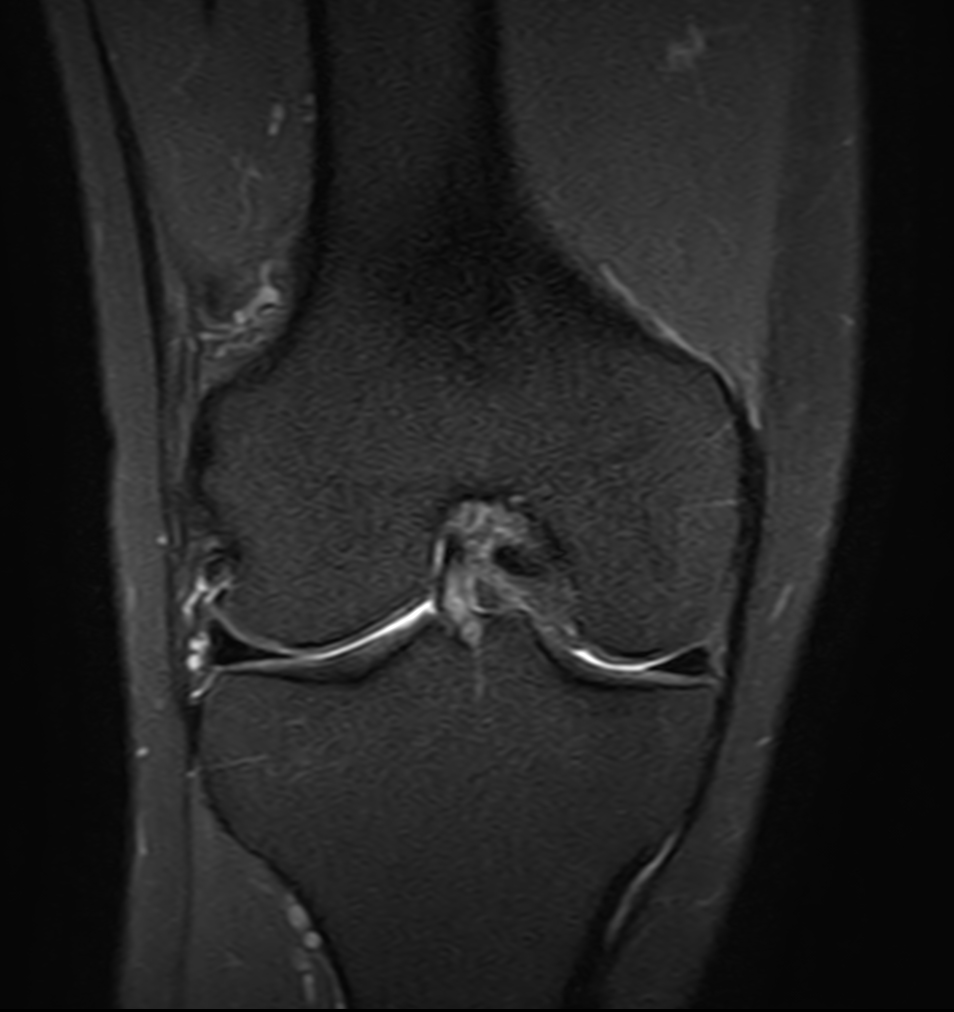

Coronal PDw TSE FatSat